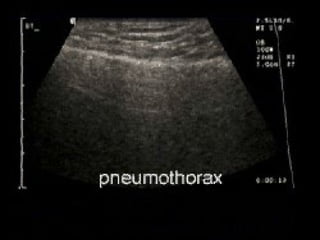

Absent lung sliding

Exaggerated horizontal artifacts

Loss of comet-tail artifacts

Broadening of the pleural line to a band

The key sonographic signs of

Pneumothorax

Absent lung sliding Exaggeratedhorizontal artifacts Loss of comet-tail artifacts Broadening of the pleural line to a band The key sonographic signs of Pneumothorax